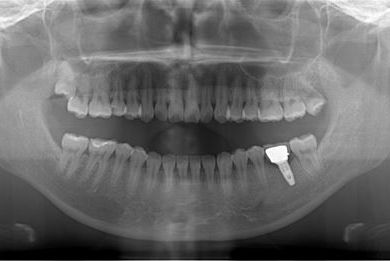

| 性別/年齢 | 女性 / 27歳 | ||||||||||||||||||||||||||||||||

| 治療方針 | インプラント治療にて、機能的・審美的回復を行う。 | ||||||||||||||||||||||||||||||||

| 治療内容 | インプラント1本、メタルボンドセラミッククラウン1本 | ||||||||||||||||||||||||||||||||

| 総治療費 | 252,000円 | ||||||||||||||||||||||||||||||||

| 治療期間 | 4ヶ月 |

インプラント埋め込み施術は外科治療のため、腫れる可能性があります。細菌感染すると施術のやり直しになりますが、当院では洗浄・滅菌を徹底して感染リスクを抑えます。また、インプラント周囲炎にならないために、通常の歯と同じように丁寧なブラッシングや定期メンテナンスが重要となります。